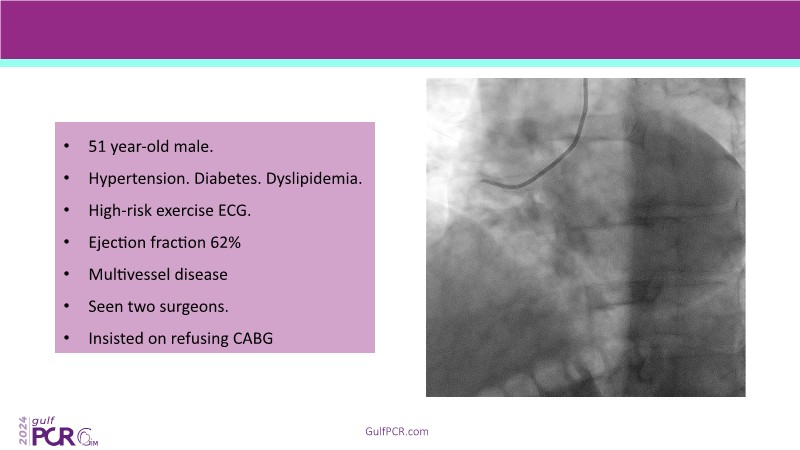

Explore cutting-edge strategies for optimizing drug-coated balloon (DCB) procedures in this session. Uncover practical tips to improve outcomes, review key indications, and examine international consensus on DCB use. Case presentations and expert discussions offer insights to refine your approach.